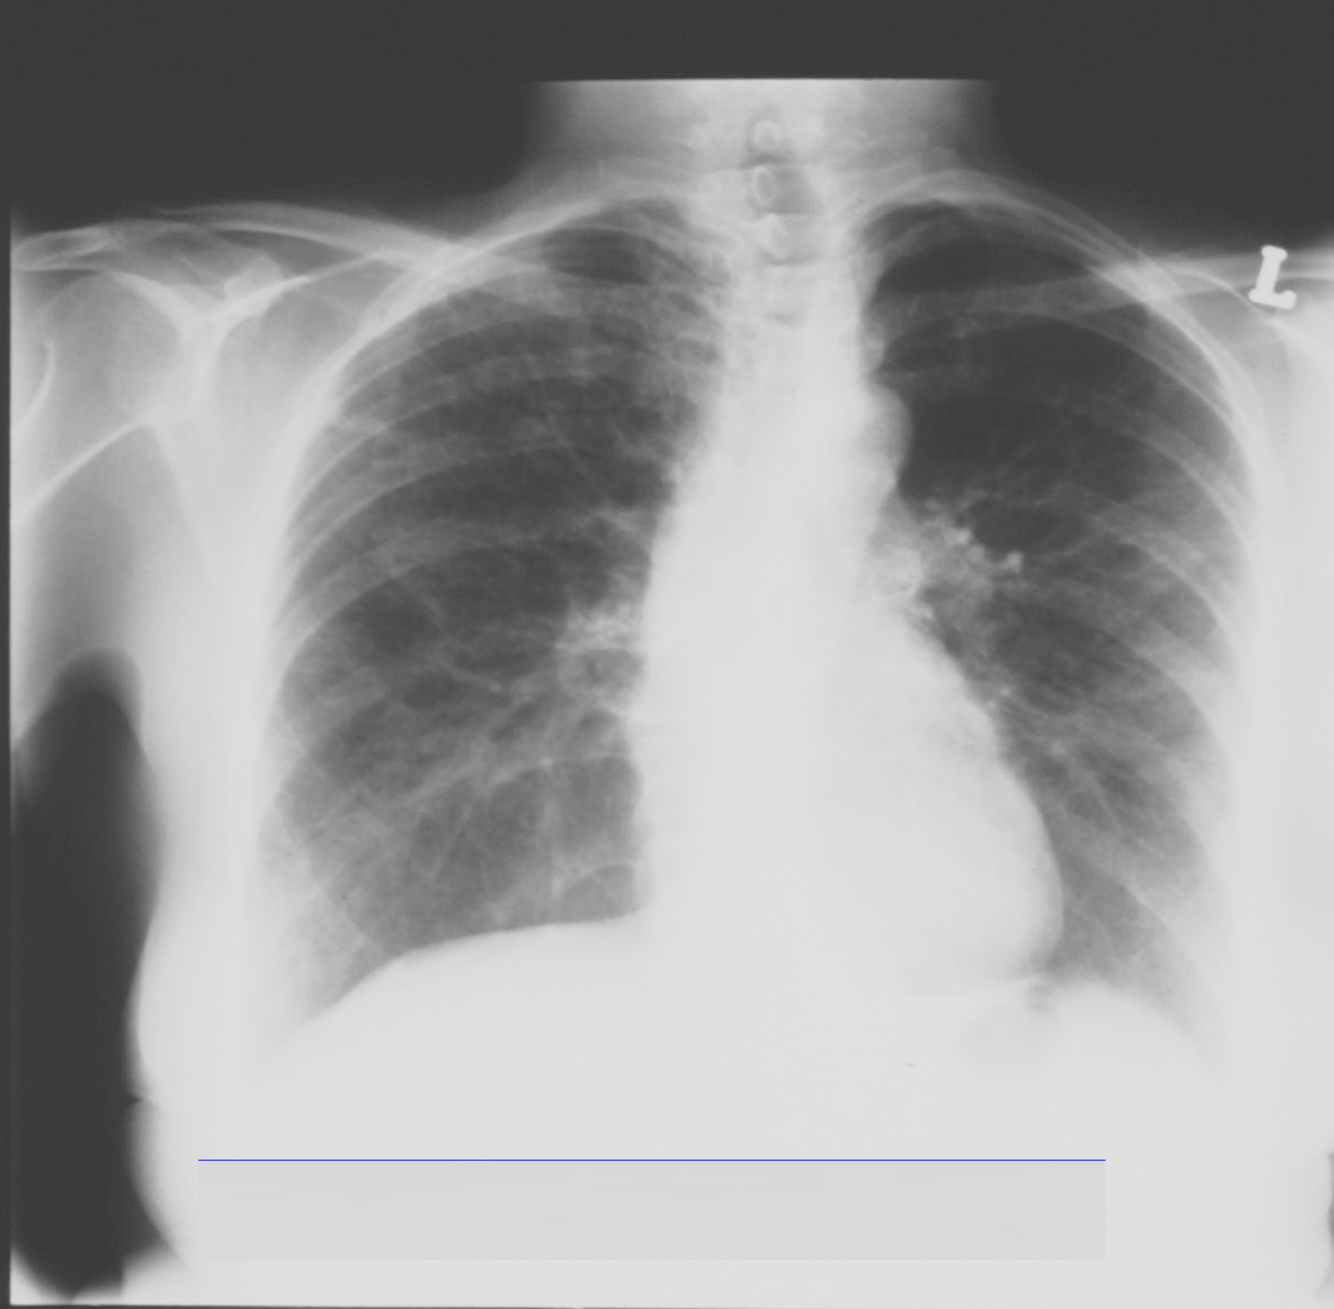

Q

What is this ?

How does idiopathic pulmonary fibrosis present ?

A

Clinical presentation: progressive breathlessness (several years), dry cough

OE: clubbing, bilateral fine inspiratory crackles

Ix: restrictive defect on PFT’s - reduced FEV1 and FVC with normal or raised FEV1/FVC ratio, reduced lung volumes, low gas transfer

CxR - bilateral infiltrates;

CT scan - reticulonodular fibrotic shadowing, worse at the lung bases, and periphery. Traction bronchiectasis. Honey-combing cystic changes.

Lung biopsy – not necessary if CT scan is diagnositic.